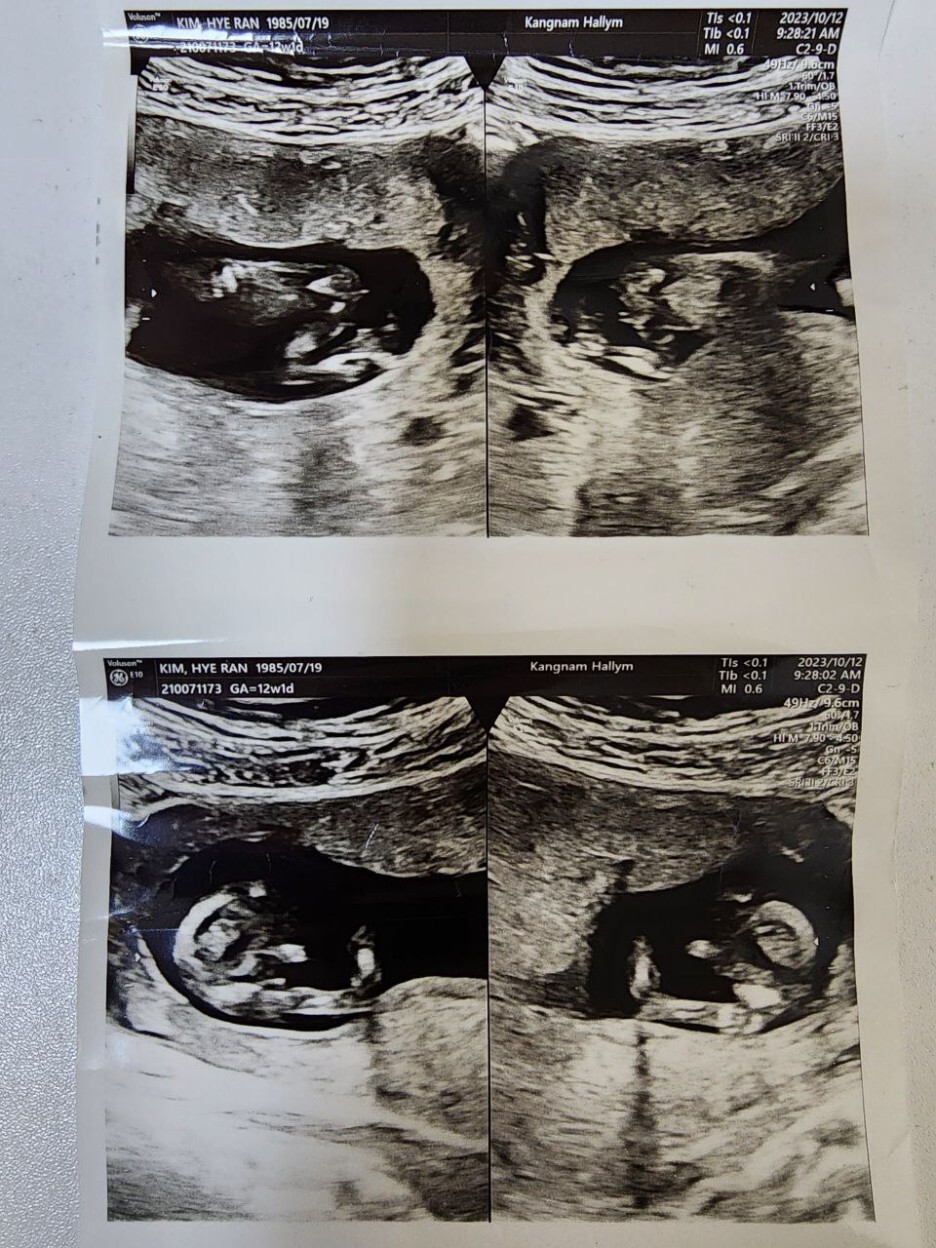

2023년 10월 12일(목요일)

CRL(Crown-Rump Length, 태아의 머리부터 엉덩이까지의 길이): 59.49mm

아기의 크기는 고작 59.49mm이지만 벌써 어느 정도 사람의 형태를 하고 있기 때문에 볼 때마다 신기할 따름이다. 특히나 다리랑 팔의 형태가 지난번에 비해 많이 뚜렷해졌다. 병원에서 12주 차부터 아기의 성별을 알려주시기도 하는데 하도 움직임이 많은 아기라 아들인지 딸인지 확인이 어렵다고 하셔서 다음을 기약하기로... 엄마는 아들이든 딸이든 다 좋아! 참고로 아빠는 딸이었으면 좋겠데! 아기를 낳고 키워보니 정말 다른 거 다 필요 없고 건강하게만 태어나고 자라주는 것이 최고의 복인 것 같더라.